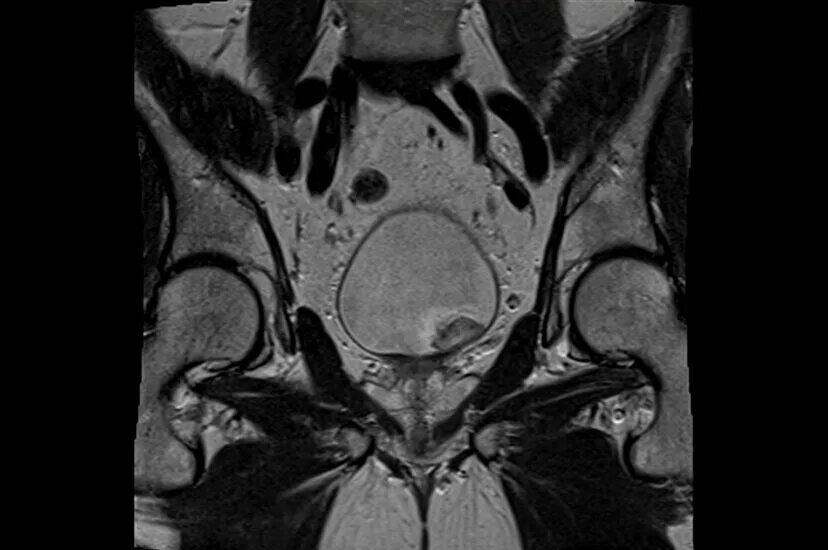

Можно ли сделать мрт малого таза